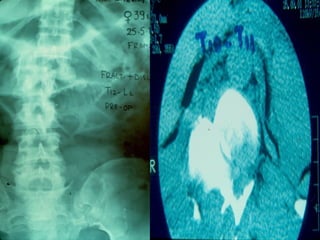

 AANN.. PPEERR..

 FF –– 2222 yyrrss

 FFaallll

 LLeevveell :: TT1122

 TTyyppee :: AA33..33

 AA..SS..II..AA.. :: EE